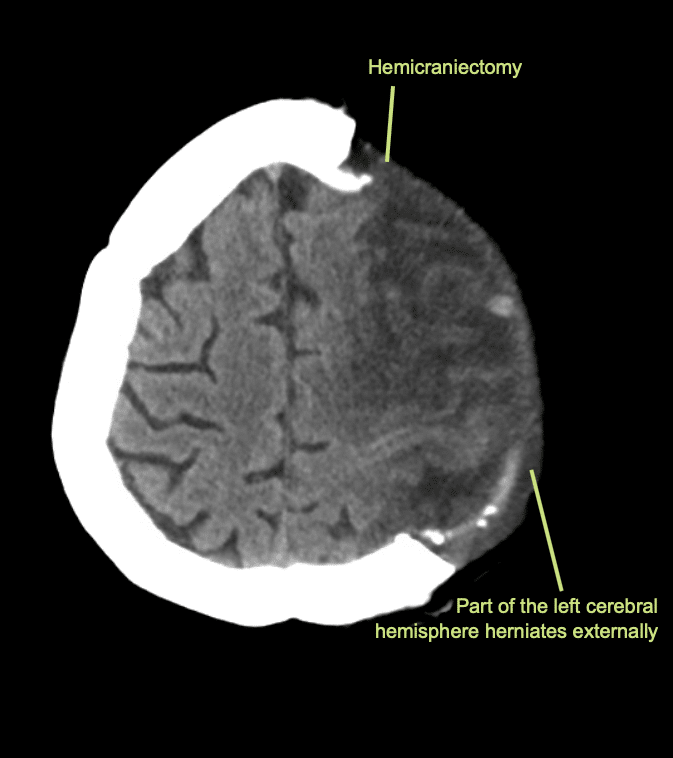

Il giorno successivo viene eseguita una TAC di controllo.

Interpretazione della TAC a 24 ore